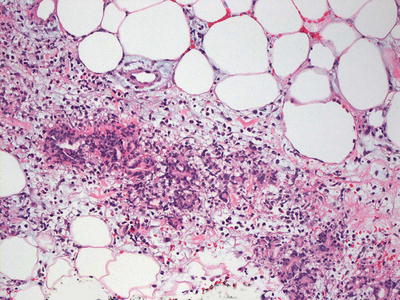

Erythema nodosum is a septal panniculitis [1]. Early lesions demonstrate septal edema and a mixed inflammatory infiltrate of neutrophils, lymphocytes, eosinophils, and occasional giant cells (Fig. 9.1). As the lesions develop, neutrophils diminish in number with increased number of histiocytes, including multinucleated giant cells (Figs. 9.2 and 9.3). Small granulomatous foci are present in some cases. The septa become thickened and fibrotic, and septal edema is less apparent. The inflammatory infiltrate may extend into the periphery of the fatty lobules, although fat necrosis is not seen. The blood vessels are not inflamed. The overlying epidermis and dermis are usually relatively unremarkable.

Fig. 9.1

Erythema nodosum demonstrates a septal panniculitis characterized by widening of the fibrous septa and an inflammatory response